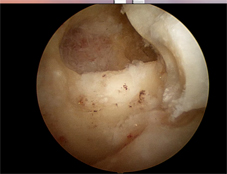

主要用來治療輕度到中度肘關節炎,同時此術式結合肘關節鏡的方式治療(如;圖二),只需要兩個小傷口就可達到切除骨刺、移除碎骨等,且有減輕疼痛的效果。只是相對於嚴重的肘關節炎來說,單用此術式就很難有效增進關節活動程度,所以必須以開放性Outerbridge-Kashiwagi術式治療(如:圖三),就可達到較佳的關節活動度。

圖二、關節鏡Outerbridge-Kashiwagi手術,從後側的入口在鷹嘴突凹窩鑿出一個窗口,可以移除前方關節腔的碎骨